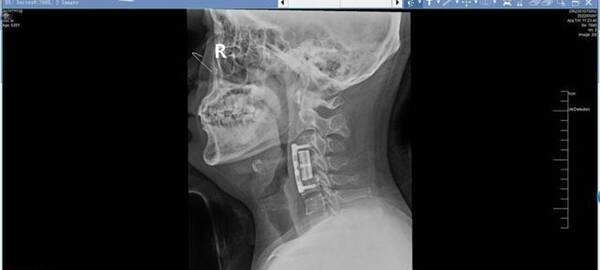

結(jié)合各項(xiàng)檢查結(jié)果,李濤院長為小陸量身制定手術(shù)方案,“頸前路椎體次全切除術(shù)+3D打印人工椎體植入鈦板重建術(shù)+椎間盤切除術(shù)”。僅用時(shí)1小時(shí),就將問題完全解決。術(shù)后當(dāng)天,小陸就覺得自己的疼痛徹底緩解了,感受到了這些天來前所未有的舒適。術(shù)后第二天,就可自行下地活動,復(fù)查X線提示為小陸定制的3D打印人工椎體與其完美適配。

記者了解到,3D打印技術(shù)是一種快速成型的增材制造技術(shù),可以根據(jù)移植部位進(jìn)行個(gè)性化定制,更加精準(zhǔn)適配人體。李濤院長介紹,鈦合金人工椎體為網(wǎng)狀多孔結(jié)構(gòu),力學(xué)性能與骨骼相近,不僅能夠減少患者痛苦,還可以縮短手術(shù)時(shí)間。